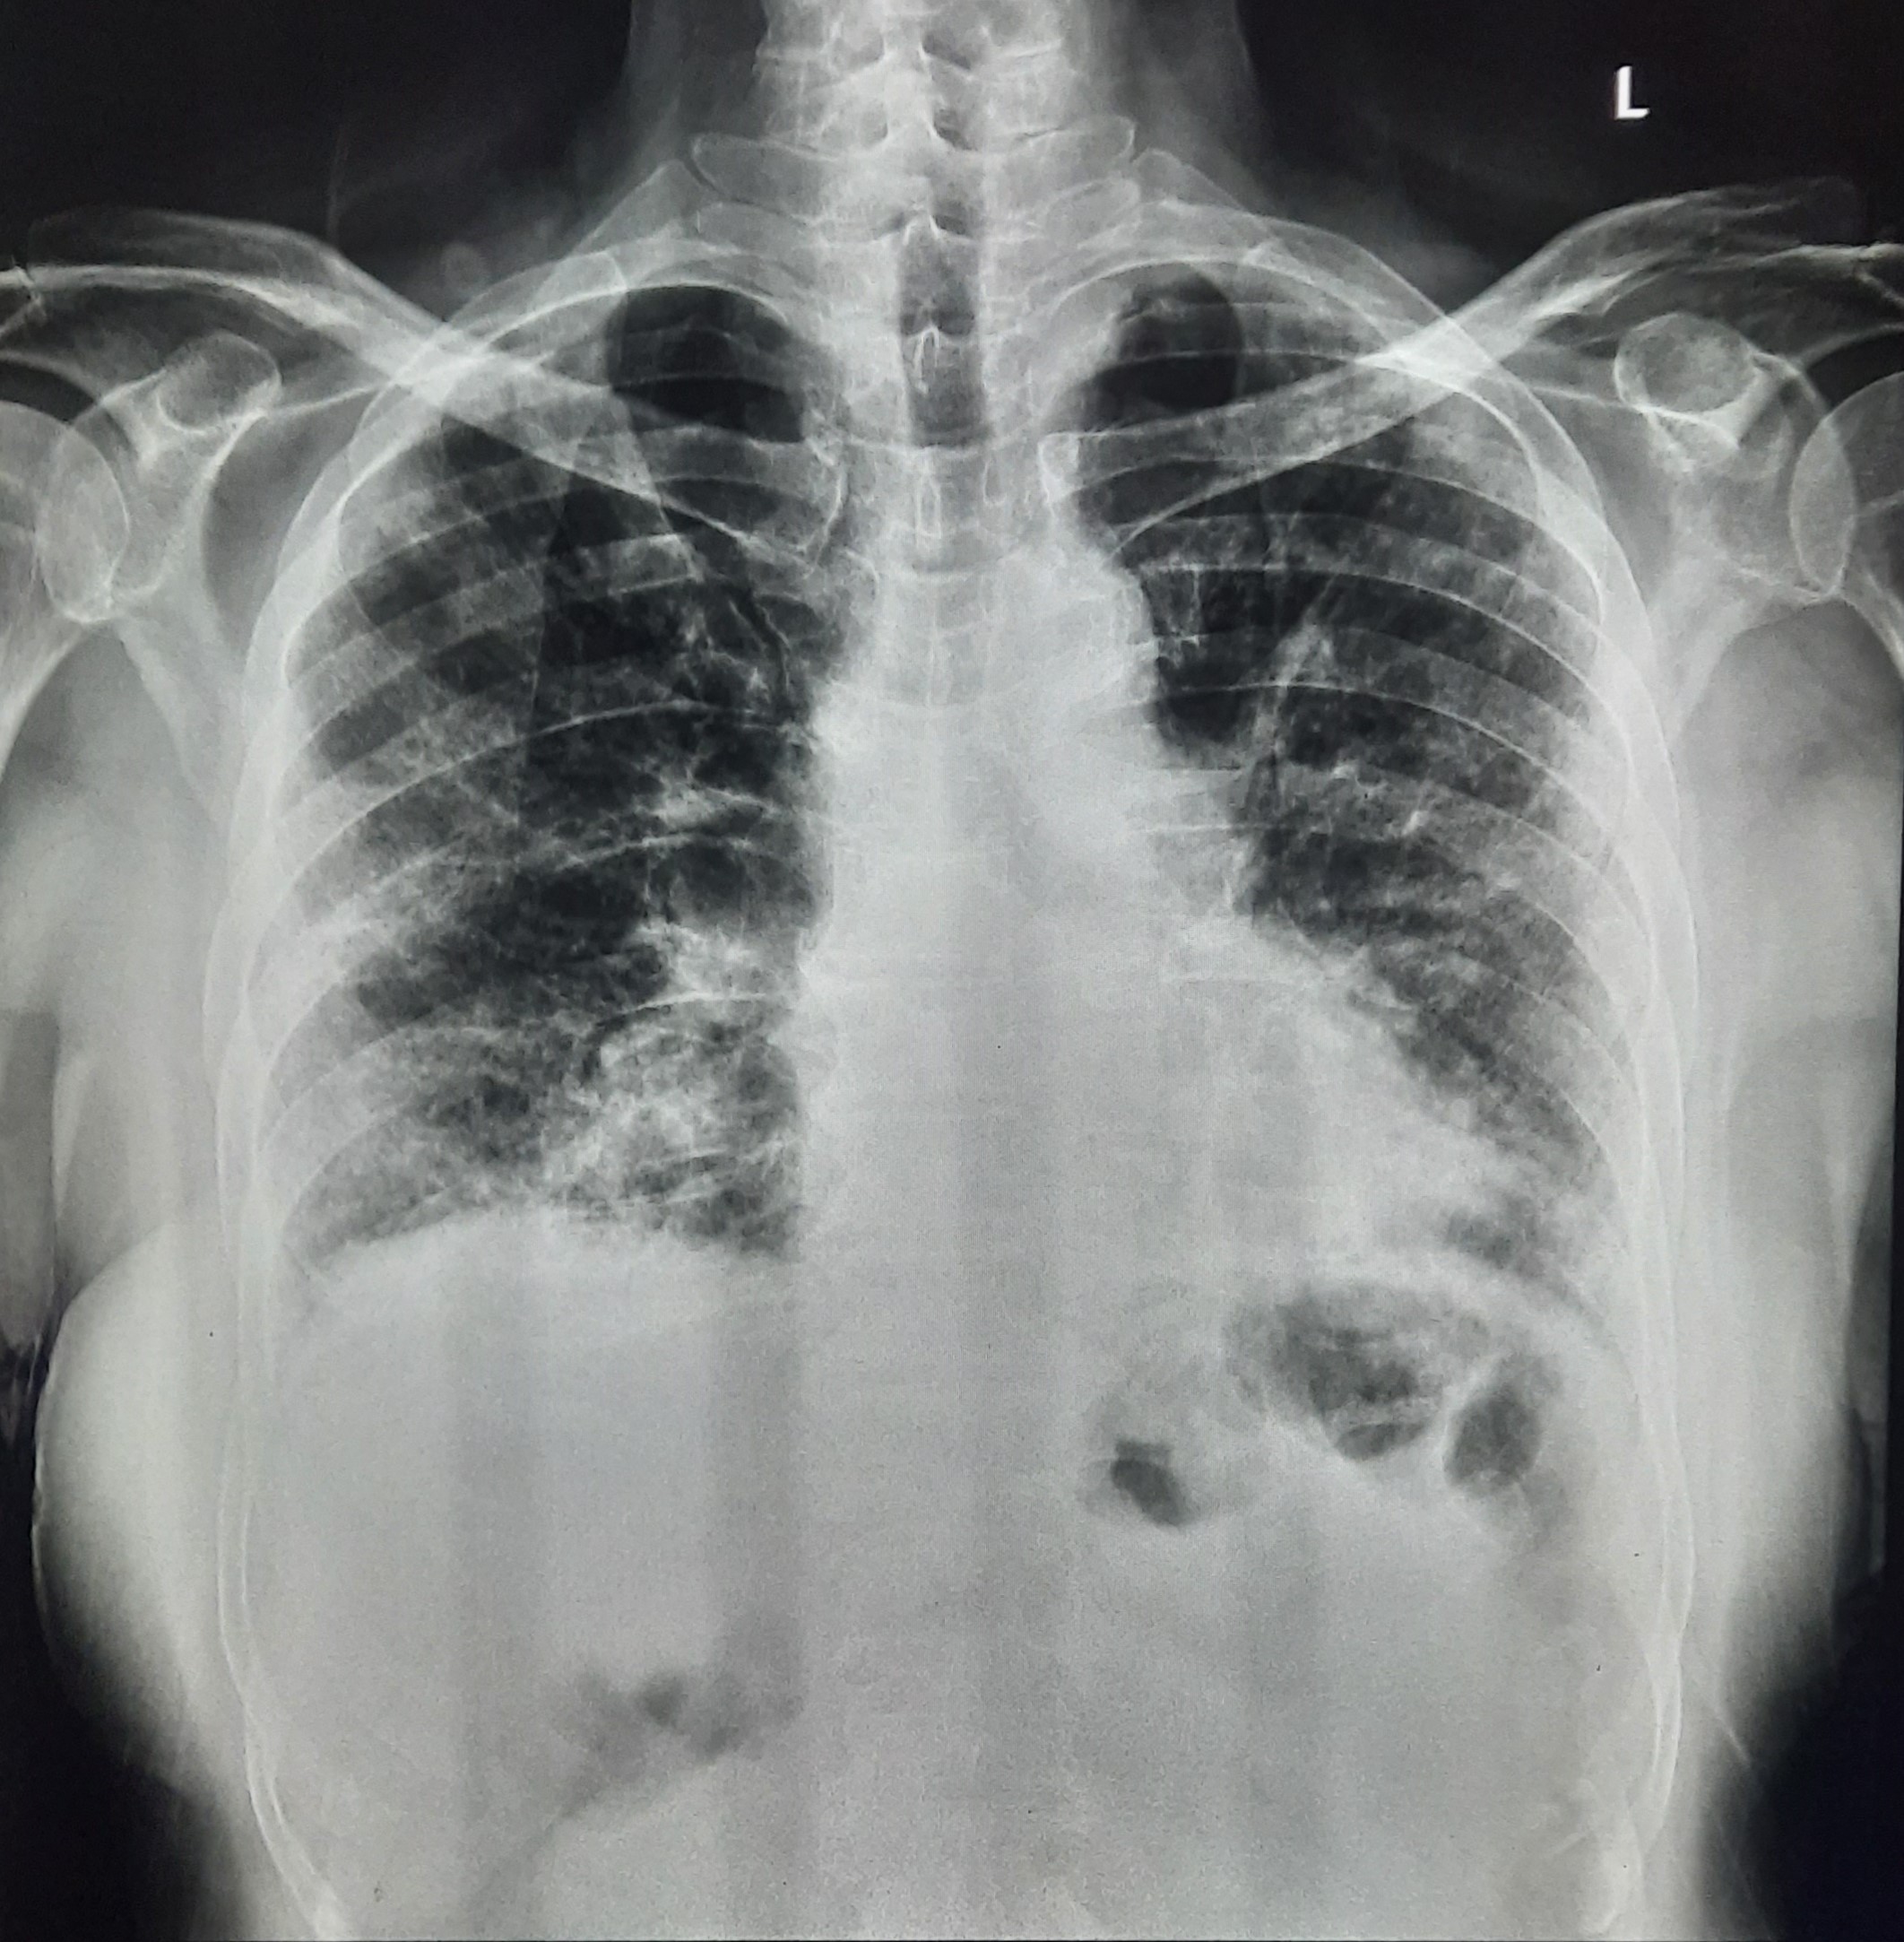

| 109 | IGGMC, Nagpur, Nagpur | P2 | 29-4363 | Leena Lokhande | Consent taken on Paper | 39 Yrs. |

Provisional Diag : Pleural Effusion

Final Diag : Pleural Effusion (Microbiologically Confirmed Right Sided Pleural Effusion) |

TB Case (Confirmed) | Bilateral Mid Zone & Lower zone Infiltration Changes Present, Right CP Angle Blunting Present, Overexposed X-ray | Abnormality visible on x-ray |